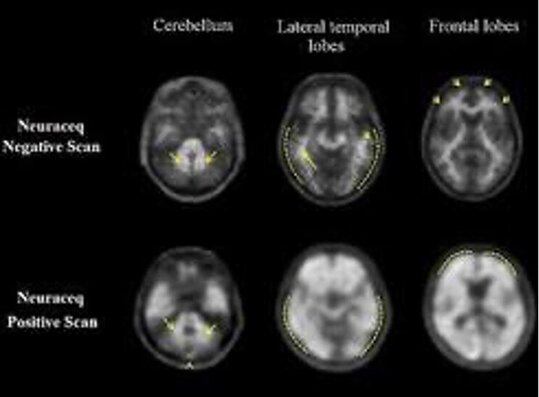

Das Amyloid-Plaque-PET/CT ist ein bildgebendes Verfahren, das wir in der Klinik für Nuklearmedizin am UKS verwenden, um Amyloid-Plaques im Gehirn darzustellen. Diese Eiweißablagerungen sind typisch für Alzheimer-Patientinnen und -Patienten und gelten als frühes Anzeichen der Krankheit. Durch die Injektion eines leicht radioaktiven Medikaments wie 18F-Florbetaben oder -Flutemetamol können wir mithilfe der PET/CT-Aufnahmen die Verteilung und Dichte der Amyloid-Plaques sichtbar machen. Dies gibt uns wertvolle Hinweise darauf, ob eine Alzheimer-Krankheit vorliegt oder ein erhöhtes Risiko besteht, aber auch auf andere Gehirnerkrankungen.

β-Amyloid-Ablagerungen sind Eiweißablagerungen, die ein typisches Krankheitsmerkmal der Alzheimer-Erkrankung sind. Die Amyloid-Plaque-PET/CT ermöglicht nun erstmals bei lebenden Patientinnen und Patienten den Nachweis der Amyloid-Plaques. Die Ergebnisse der Untersuchung müssen immer zusammen mit der Anamnese – also der im ärztlichen Gespräch erhobenen Krankengeschichte – interpretiert werden. Bei einem negativen Untersuchungsergebnis, also wenn keine Plaque gefunden wird, kann eine Alzheimer-Erkrankung jedoch sicher ausgeschlossen werden.